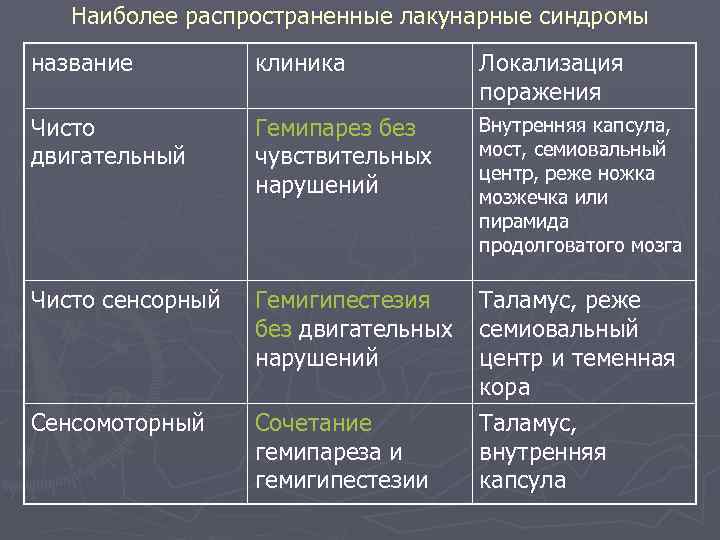

Наиболее распространенные лакунарные синдромы название клиника Локализация поражения Чисто двигательный Гемипарез без чувствительных нарушений Внутренняя капсула, мост, семиовальный центр, реже ножка мозжечка или пирамида продолговатого мозга Чисто сенсорный Гемигипестезия без двигательных нарушений Сенсомоторный Сочетание гемипареза и гемигипестезии Таламус, реже семиовальный центр и теменная кора Таламус, внутренняя капсула